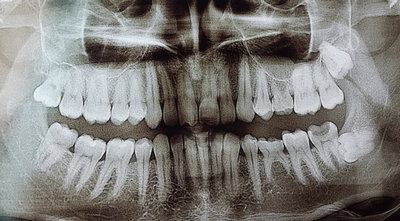

У меня два нижних зуба мудрости выросли неправильно, т.е. горизонтально, вылезли не полностью, а частично торчат. Один уже с кариесом и даже откололся.

Стоит ли удалить два нижних ретенированных зуба мудрости одновременно?

Вообще, рекомендуется удалять ретенированные 8-е зубы по одному (максимум по два), так как это довольно длительная и сложная манипуляция. Пациенту сложно просидеть так долго с широко открытым ртом.

Таким образом, моё мнение, лучше удалять по одному, причём с перерывом в несколько недель, если зубы не беспокоят.